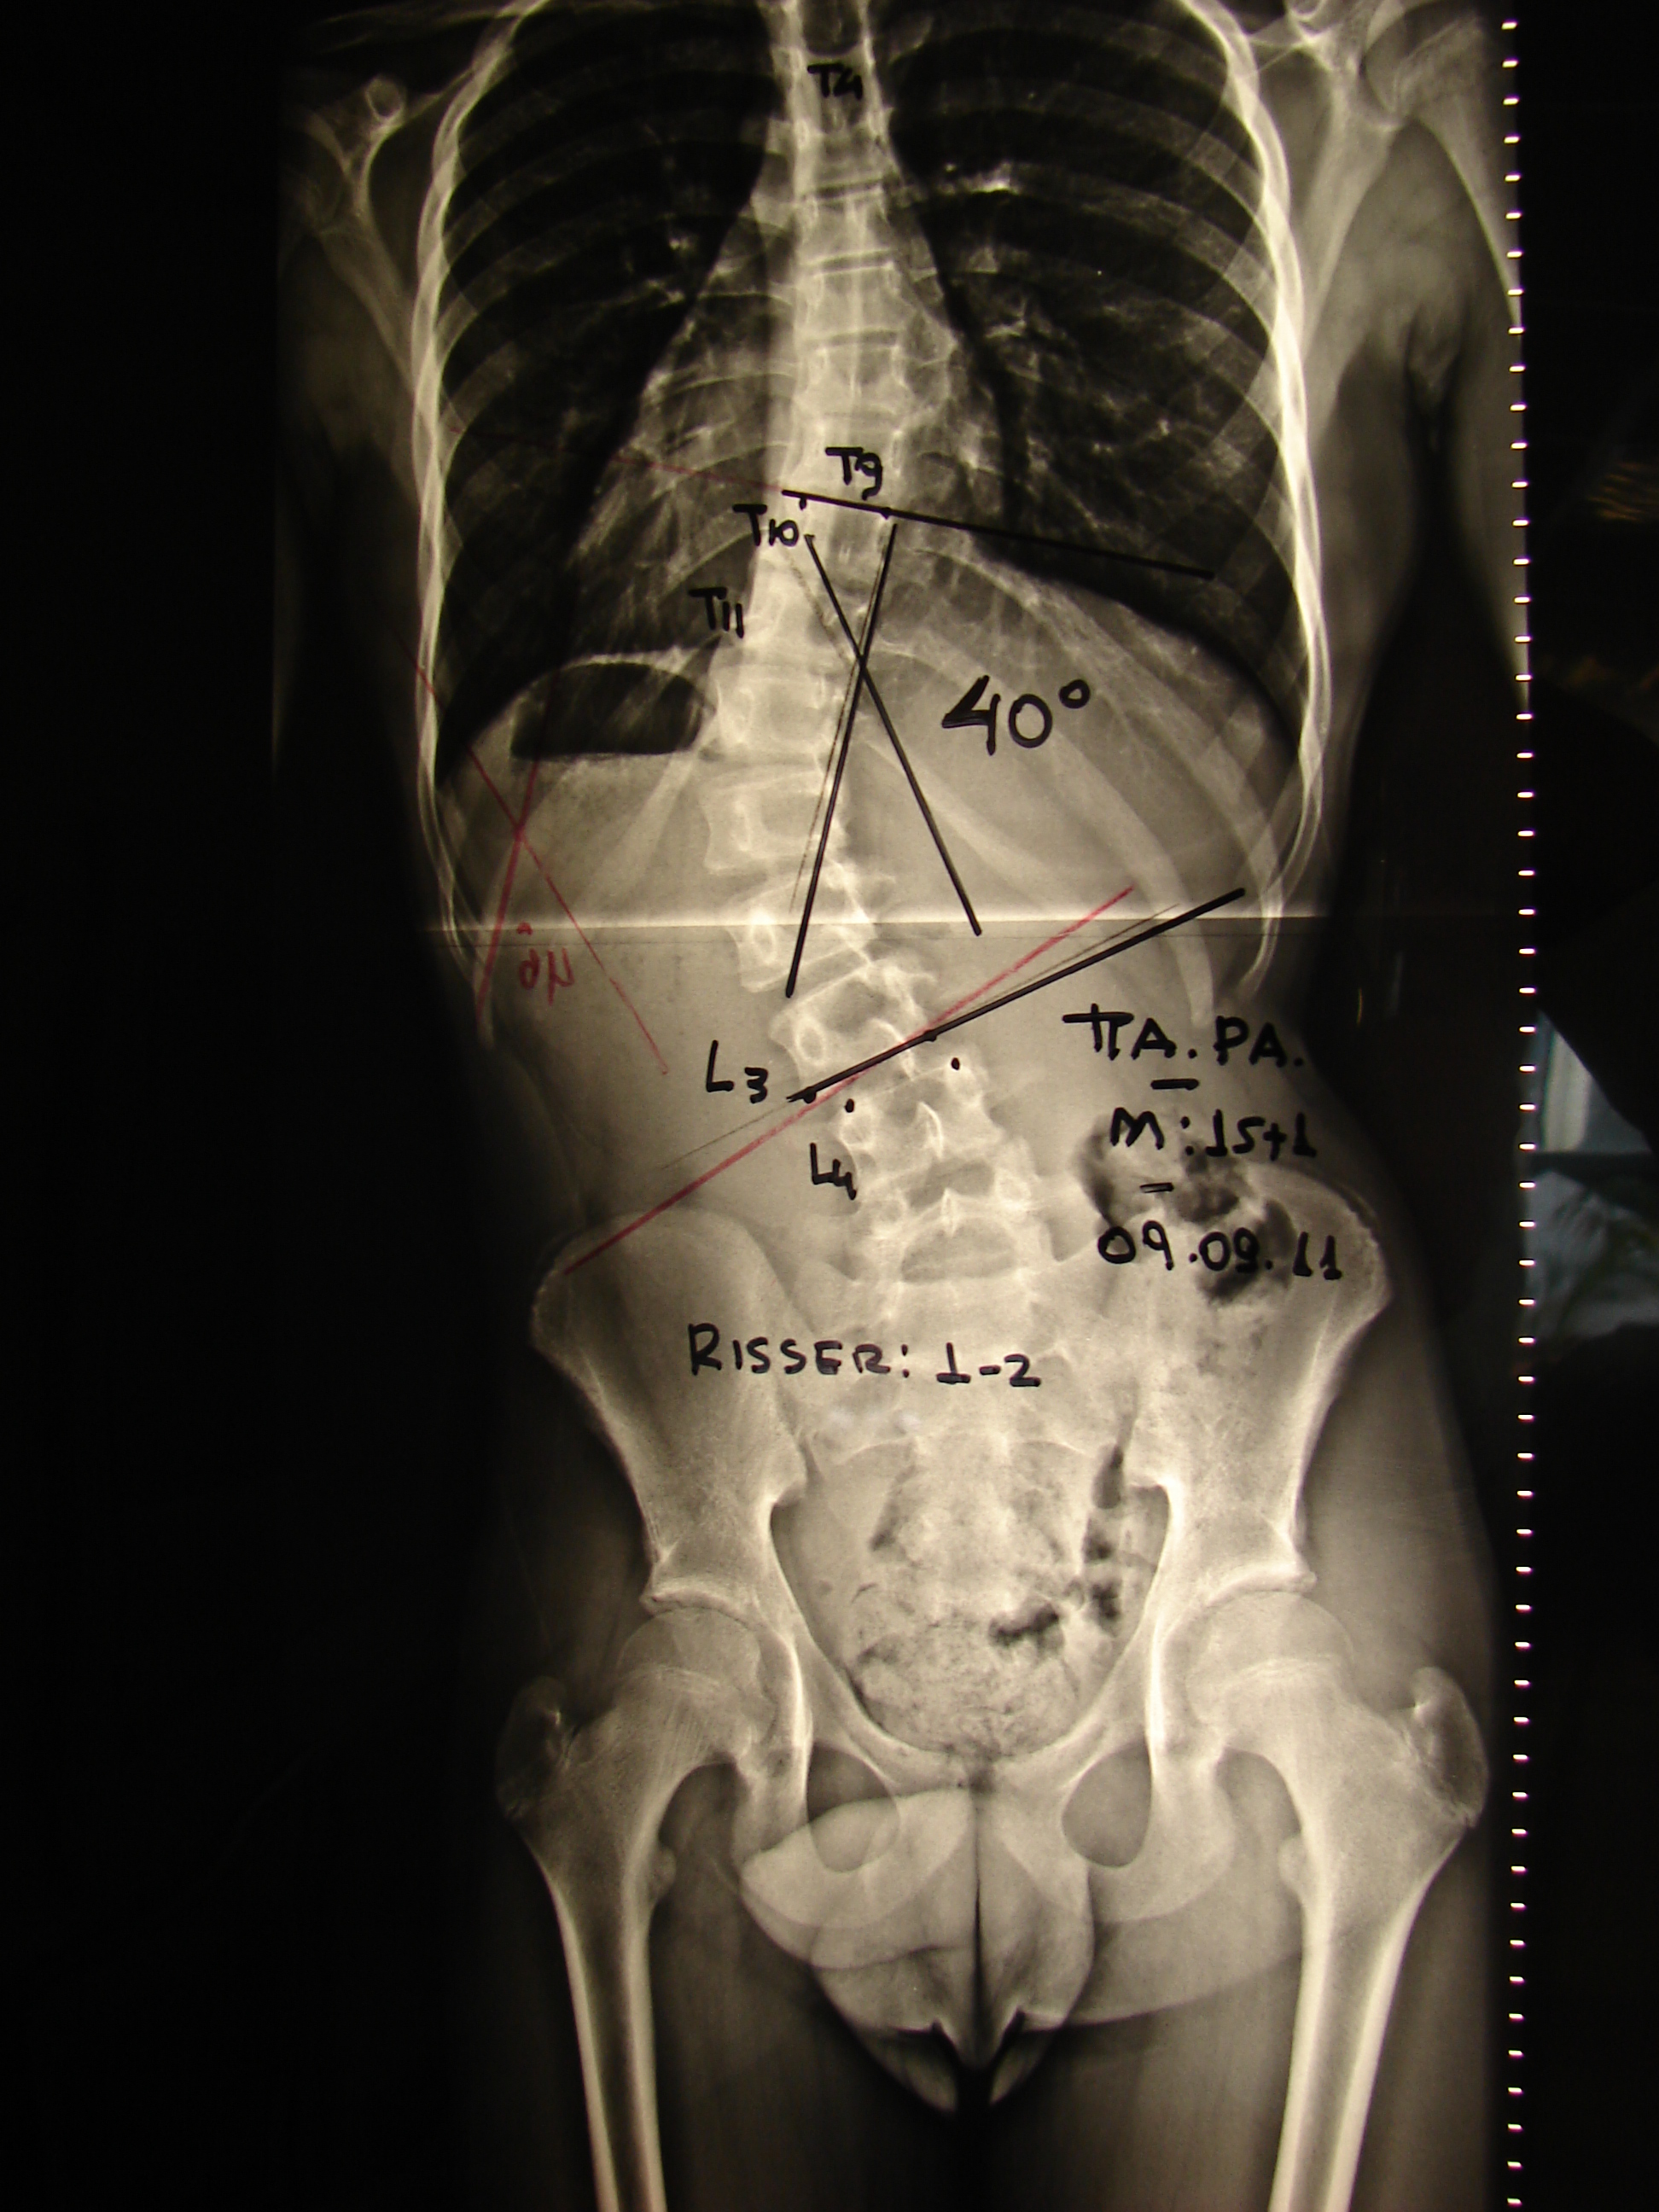

Εικόνα 3 α,β,γ

Προεγχειρητική μαγνητική τομογραφία. Δεν αναδεικνύεται η ύπαρξη παθολογικής επεξεργασίας της σπονδυλικής στήλης και του νωτιαίου μυελού.